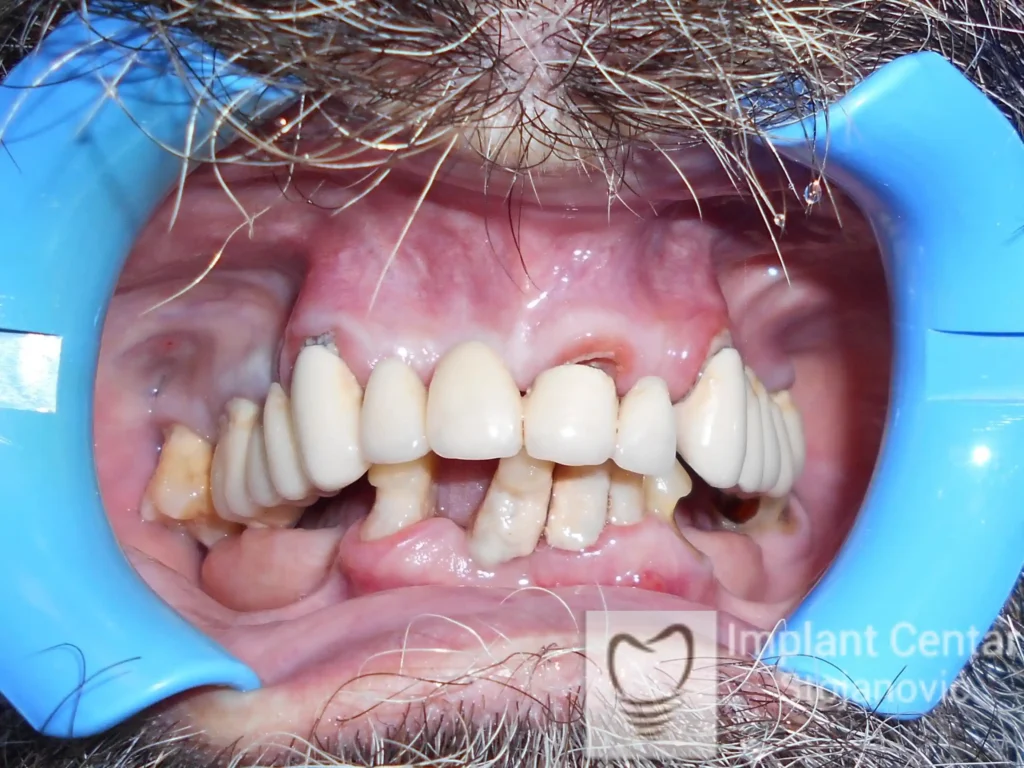

Nakon detaljnog kliničkog pregleda i analize radioloških snimaka, izrađen je sveobuhvatan plan terapije sa ciljem uklanjanja mobilnih proteza i postizanja maksimalne funkcionalne i estetske rehabilitacije. Zbog loše biološke vrednosti preostalih zuba, doneta je odluka o njihovom vađenju i ugradnji dentalnih implantata.

Poseban terapijski izazov predstavljalo je premošćavanje defekta nastalog usled rascepa, kao i ograničena količina raspoložive kosti u gornjoj vilici. Primenom većeg broja implantata i odgovarajućih procedura nadoknade kosti, postignuta je stabilna osnova za fiksni protetski rad.

Tokom perioda oseointegracije, pacijent je bio zbrinut fiksnim privremenim krunicama, čime je već pet dana nakon intervencije obezbeđena potpuna funkcionalna i estetska rehabilitacija. Nakon završetka perioda integracije implantata, izrađeni su definitivni cirkonijum-keramički mostovi na implantatima.